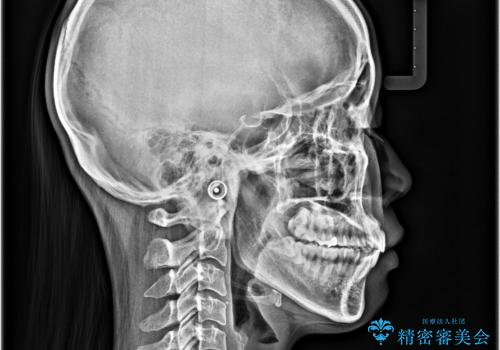

- くちばしのように飛び出した前歯を気にして来院された患者様です。

上下左右の第一小臼歯4本を抜歯して、ワイヤー装置にて矯正治療を行うこととしました。

舌の突出癖により、口元が突出しているだけでなく、上下前歯が非接触となっておりました。

舌のトレーニングをしっかりと行っていただくことで、2年を切って治療を終えるとともに

、上下前歯を接触させることができました。